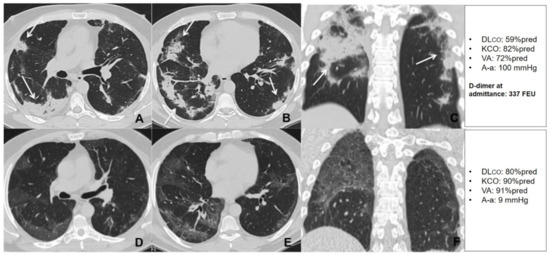

Figure 7.

Unenhanced thin section axial (A,B) and coronal (C) CT images of the lungs obtained the 10th day post-admission in a 51-year-old man with no previous exposure to cigarette smoke, no cormorbidities, that was admitted to the high dependency respiratory care unit (HDRU) with severe respiratory failure (PaO2/FiO2 182 mmHg) and treated with continuous positive airway pressure (CPAP) for 10 days. The images show peripheral consolidations (arrows) in both lungs, with predilection for posterior areas. Unenhanced thin section axial (D,E) and coronal (F) CT images of the same patient 6 weeks post-discharge show bilateral peripheral GGO with resolution of previous consolidations. The patient had a low D-dimer at admission and showed a significant improvement in his DLco during the recovery period.